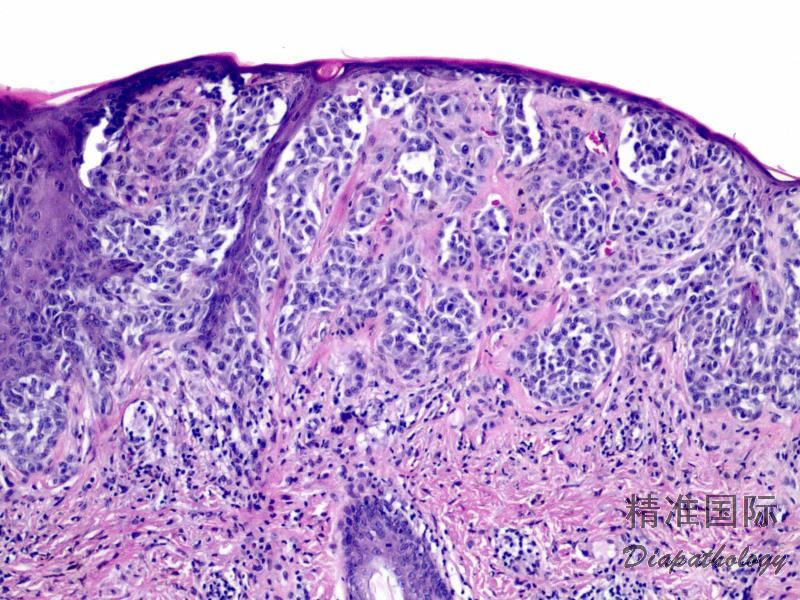

原位黑色素瘤伴异型黑色素细胞真皮浸润,无分化成熟;

典型病例表皮-真皮交界处细胞生长活跃使得表皮-真皮分界模糊,单个或成簇细胞 Paget 样表皮内扩展;

表皮内扩张(Paget 样)

吞噬上皮脚,上皮脚消失,上皮变薄;